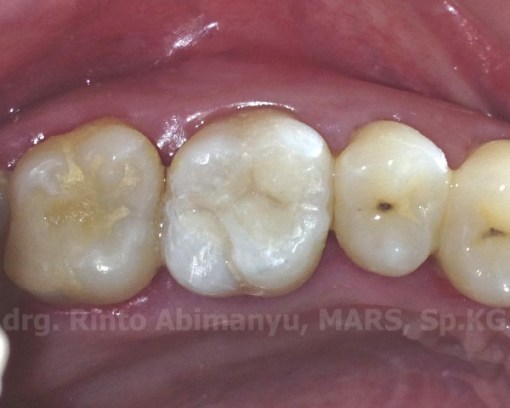

Ini kondisi saat datang sebelum tambalan sementara dibongkar…

Ini dia foto giginya setelah selesai perawatan..